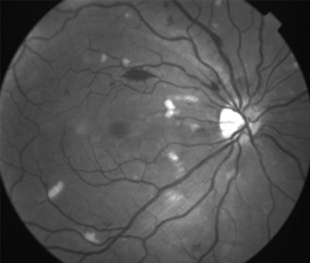

Angiopatía retiniana traumática con manchas algodonosas, extravasación linfática después de aumento de presión intracraniana.

- Bilateral, 20/200 a CD, alteración de la capa de fibras nerviosas, atrofía disco óptico.

- Angiografía: teñido arterial, escape capilar, más tardíamente, no perfusion arteriolar y venular con teñido de las paredes vasculares y dilatación venosa.